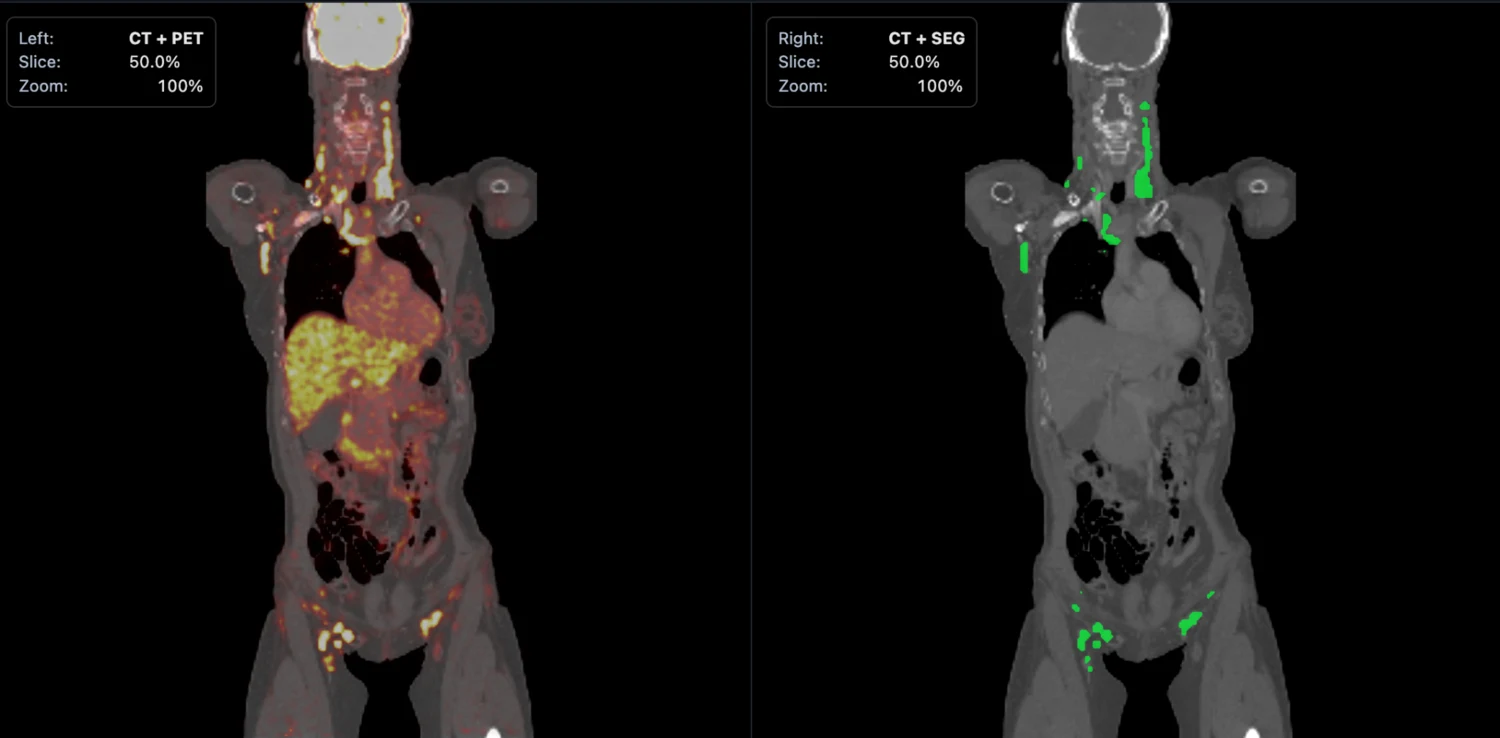

Left: the PET/CT scan.Right: the segmentation mask generated by the software.

The PET/CT image shows the scan with abnormal uptake in context. The segmentation image shows what the model has isolated as disease. Once that mask is created, the rest of the pipeline can measure tumor burden and export structured case-level results automatically.

PET/CT input shows where abnormal uptake appears Segmentation output shows what the model marks as disease

Side-by-side PET/CT input and segmentation mask output from the interactive sample case

From scan to measurable mask This is the core workflow: start with the PET/CT image, create the segmentation mask, then extract quantitative outputs from the masked disease volume.